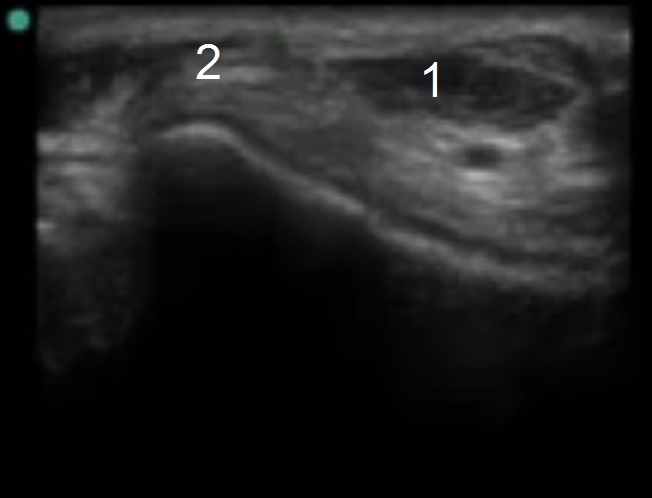

Image 2 - Pied et cheville, anatomie du tendon extenseur

1. Tendon long extenseur de l'hallux

2. Tendon long extenseur du doigt